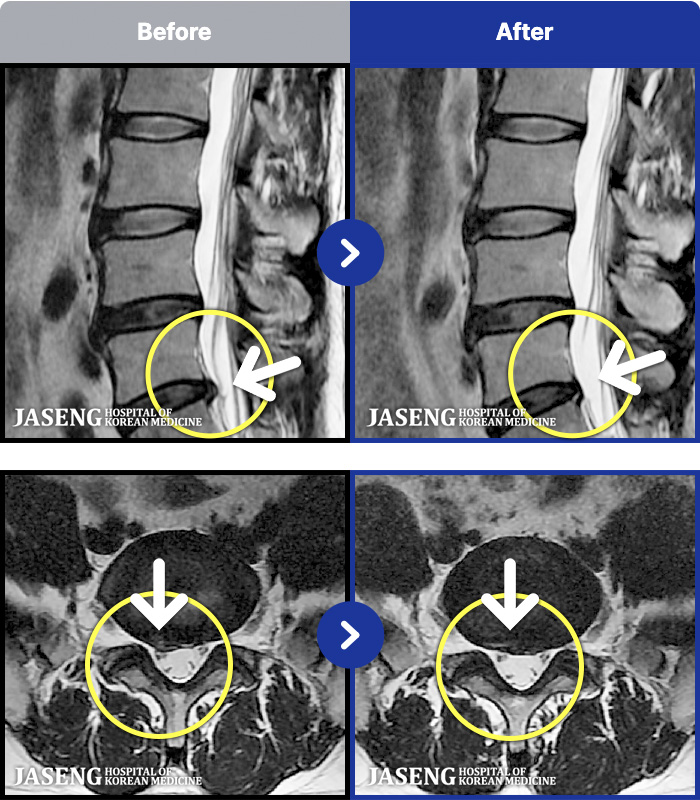

1,286 MRI ũ ʸ Ȯϼ.

[ϻ] 24.07.25~25.08.01